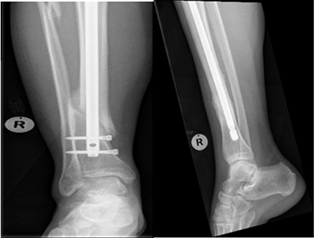

At final follow-up assessment in 9 months post-surgery, on anteroposterior view, 68.0% of cases demonstrated acceptable union, while 28.0% showed malunion, and 4.0% resulted in non-union. On the lateral view, 93.0% of cases exhibited acceptable union, with 3.0% showing malunion and 4.0% resulting in non-union. The overall union rate, as measured by the RUST score, was 96.0%, with 4.0% resulting in non-union (Figure 5 & 6).

Figure 5 Nonunion post IMN.

Figure 6 Nonunion post plate fixation.